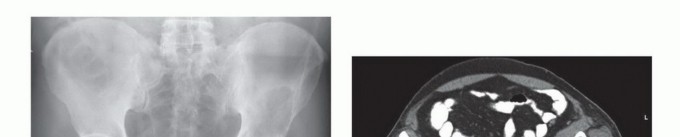

- الأشعة السينية (X-rays): هي الفحص الأولي، ويمكن أن تكشف عن التغيرات العظمية مثل التآكل أو التصلب أو الكسور.

- التصوير المقطعي المحوسب (CT Scan): يوفر صورًا مقطعية مفصلة للعظام والأنسجة الرخوة، ويساعد في تحديد حجم الورم، مدى انتشاره داخل العظم، وعلاقته بالهياكل المحيطة.